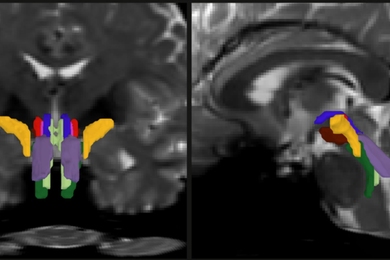

The proposed supramolecular polymer gel network. Structures in yellow are synthesized polymer; structures in purple are linear polymer; and the red structures are inter-polymer hydrogen bonds.